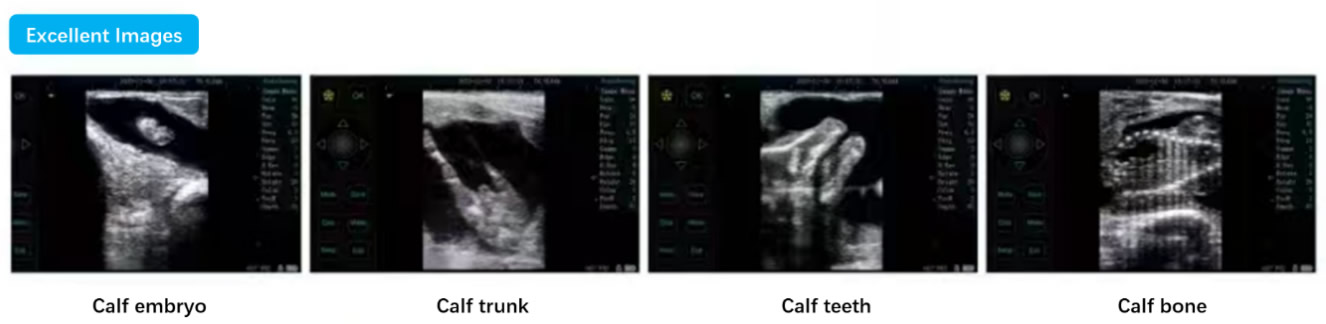

✅ Excellent Imaging for Veterinary Diagnostics

· Calf embryo

· Calf trunk

· Calf teeth

· Calf bone